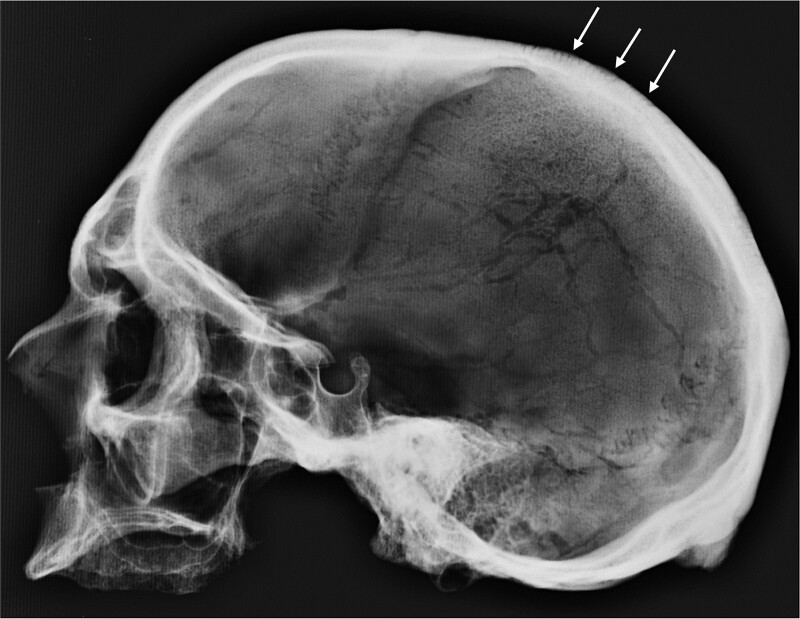

Human remains in a state of advanced decomposition were discovered in a wooded area in Mecklenburg County, North Carolina in June of 2021. Based on anthropological analysis conducted at NCSU in June of 2022, the decedent was estimated to be a 30- to 50-year-old European-American male, with a mean stature of 5 feet 5 inches (1.651 m) [2, 33–35]. The hair-on-end appearance or the perpendicular trabecular proliferation resulting from severe anemias was visible on the postmortem radiographic images (Figure 2) [36]. No perimortem trauma was observed on the remains available for analysis. Bone samples were selected for DNA extraction and sequencing, and isotopic analyses (87/86Sr, δ13C, δ15N) in 2022.

Figure 2.

Lateral radiograph of the cranium of Identified Mecklenburg John Doe 2021 showing hair-on-end appearance (arrows) indicative of anemia.